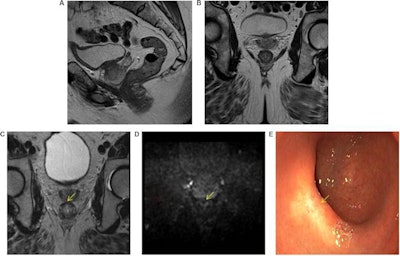

In rectal cancer -- Beets-Tan's own specialty -- local recurrence rates after surgery were as high as 40% before the widespread use of MRI classification of tumors based on molecular risk factors was established in the early 2000s. With the added benefit of identifying cancer in surrounding tissue, the recurrence rate has dropped to approximately 3%.

To that end, advances will come by combining imaging with other biomarkers, such as those used in radiogenomics, according to Beets-Tan, who won the Most Effective Radiology Educator award in the 2019 EuroMinnies. In a recently submitted study, for instance, Beets-Tan and colleagues developed a panel of mutations in genes of different tumor types that drive the development of colon cancer.